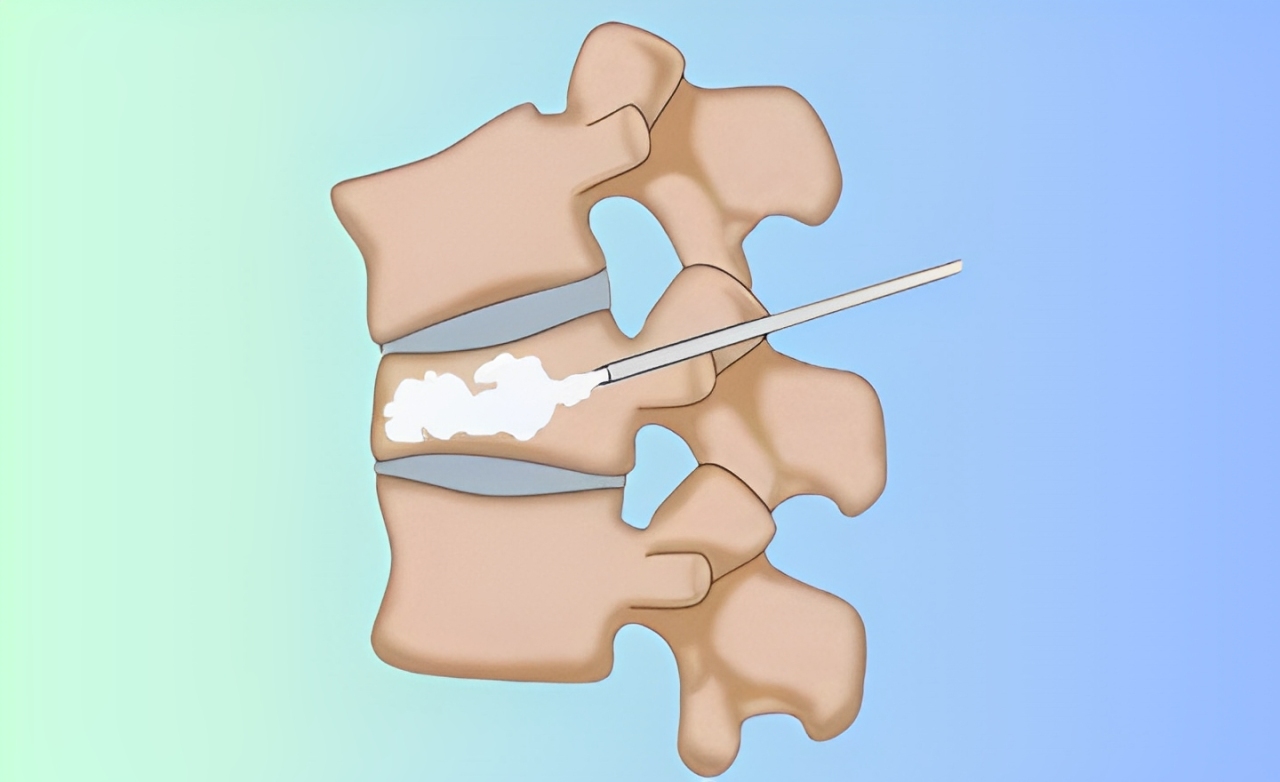

A minimally invasive procedure injecting bone cement into fractured vertebrae, stabilizing the spine, relieving pain, and restoring mobility in patients.